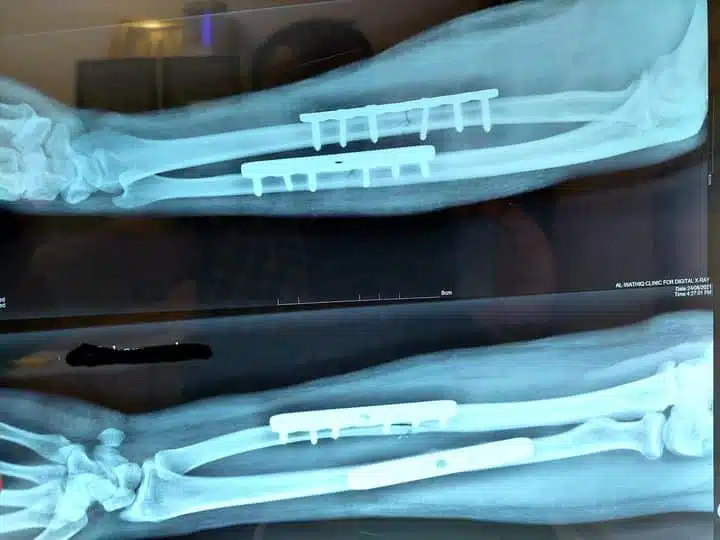

عملية الشرائح والمسامير تعتبر أحد الإجراءات المهمة التي يستعين بها الأطباء من أجل تثبيت العظام في حالة تعرضها لكسور شديد، ويتم استخدام بعض التقنيات الطبية الحديثة التي تساعد على تركيب الشرائح في العظام بعد إزالة المكسور ومتضرر منها وتثبيتها بالمسامير ومن أهمها المناظير، وتعتبر من الإجراءات الطبية الناجحة والتي أثبتت فاعليتها وجعلت المريض يستعيد العضو وظيفته.

- يبدأ بوضع الطعوم العظمية في حالة الحاجة إلى ذلك ووضع الشرائح بين العظام وتثبيتها بالمسامير.